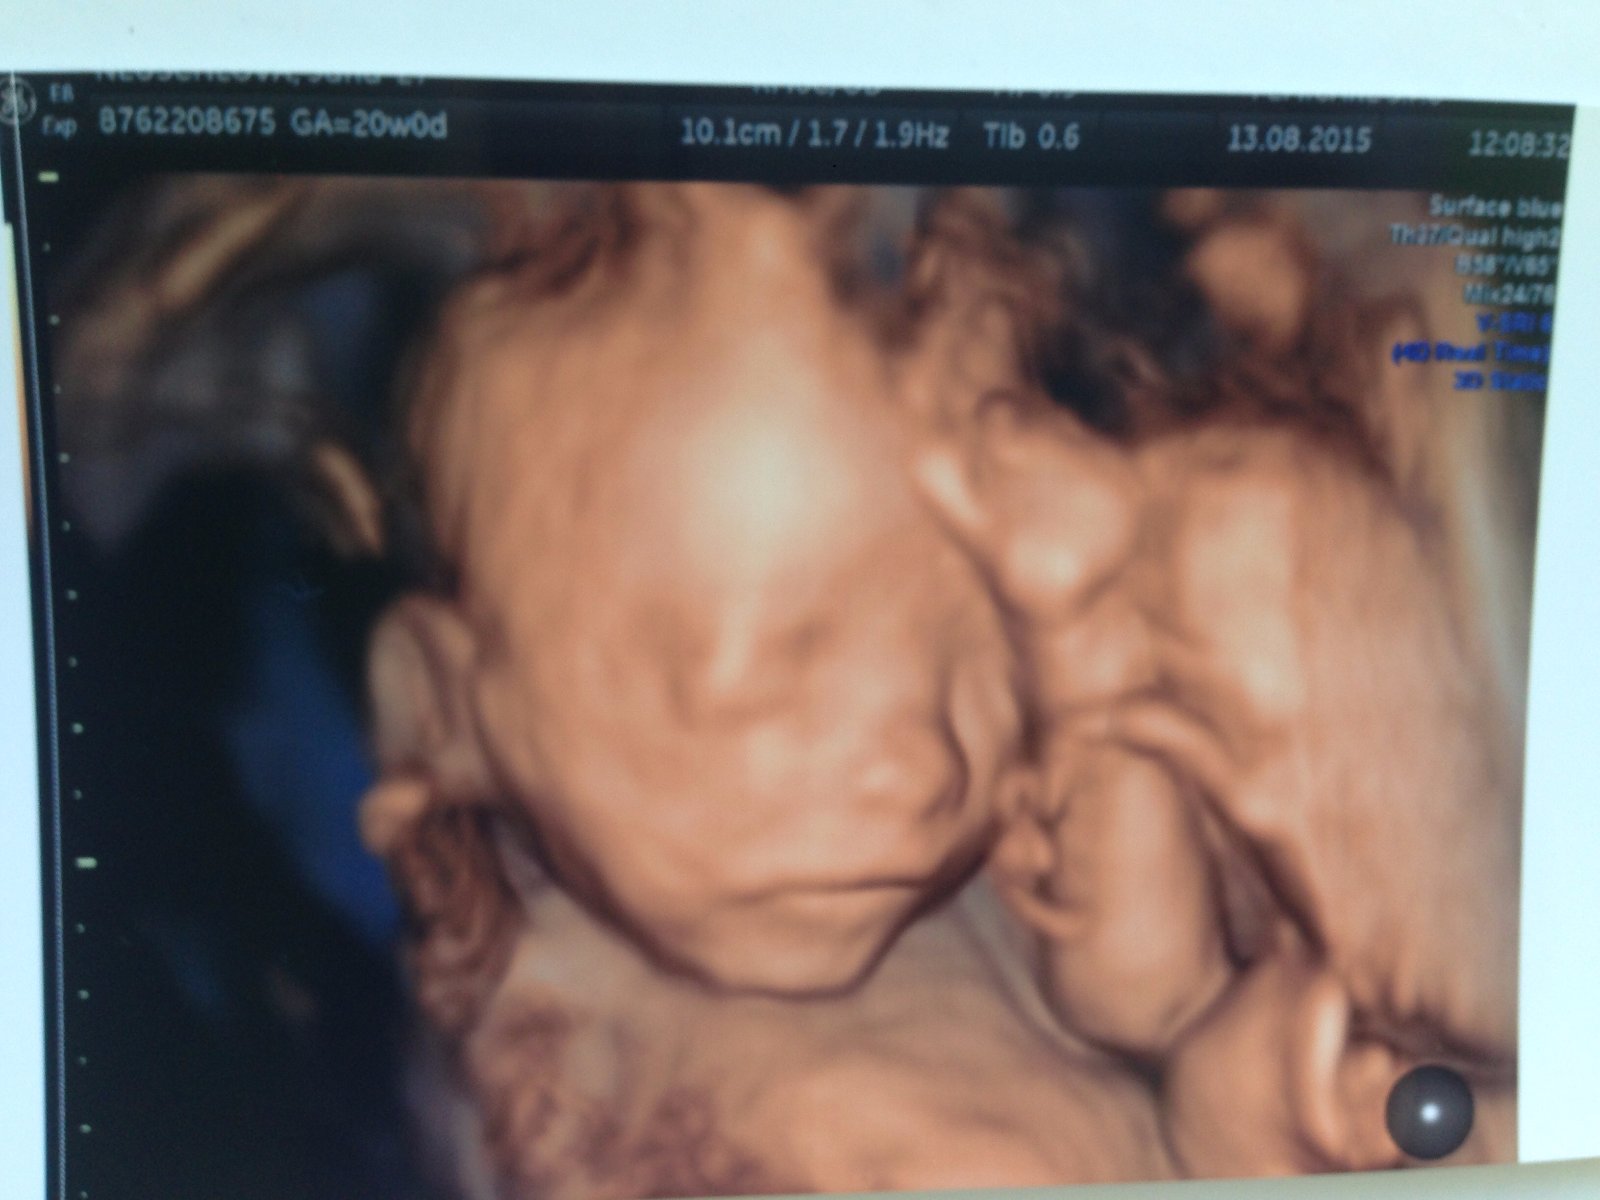

@gabuchah ňuňuška krásna malinká 🙂 pridávam aj našú foto z 20. tt

@55minnie55 krásna, ako si ležká 🙂 to je zlaté 🙂 vaša teda viac spolupracovala 🙂

@666maybe no ono to tu nejde zmazať, ani príspevky čo som si všimla ale nevadí, takéto rozkošné fotky môžu byť kľudne aj 5x za sebou 🙂 a tú ručičku na čele ako má 🙂 naša pod bradou, to budú myslitelky 🙂 🙂

@gabuchah ani pan boh nevie po kom je, kazdy hovori inak a nam s priatelom sa podoba na Angela z Kelly Family 😀 po bokoch tie akoze blond kucery chiiiiii 😀 Ked sme tam boli a zacal mi ukazovat tu ma plece, tu nozicku, tu srdiecko ..pozeram do kelu ja tam nic nevidim :D ale ked mi to hodil 3d a ukazal mi tvar tak sme s drahym ani nedychali (vtedy si on asi prvykrat uvedomil ze bude tato 🙂 najradsej by som k nemu chodila kazdy tyzden ...uz si len na tie nase drobciatka pockat 🙂